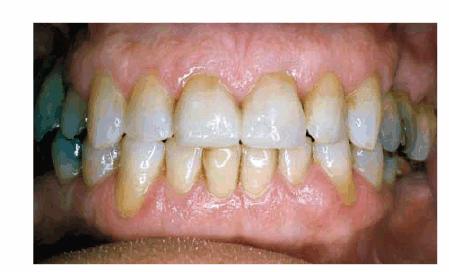

Figure 29-9A shows an older man with discolored and worn

teeth and irregular gingival margins. This combination contributed to his

unattractive smile. He requested a younger-looking smile. His treatment plan

consisted of periodontal surgery to improve the gingival contours and five

porcelain veneers plus posterior crowns and inlays. Figures 29-9B, and 29-9C show the final result with lighter teeth and improved

tooth shape and arch alignment.

Figure 29-9A: This chief executive officer had discolored and worn teeth and irregular-looking gum tissue, resulting in an aged smile. (Reproduced with permission from Goldstein RE. Change your smile. 3rd edn. Carol Stream, IL: Quintessence, 1997:243.)

Figure 29-9B: After cosmetic periodontal surgery, during which the gingiva was cosmetically and functionally improved, five porcelain laminates were placed, as well as posterior crowns and inlays.

Figure 29-9C: The result was lighter teeth and improved tooth shape and arch alignment to help create a younger-looking smile. (Reproduced with permission from Goldstein RE. Change your smile. 3rd edn. Carol Stream, IL: Quintessence, 1997:243.)